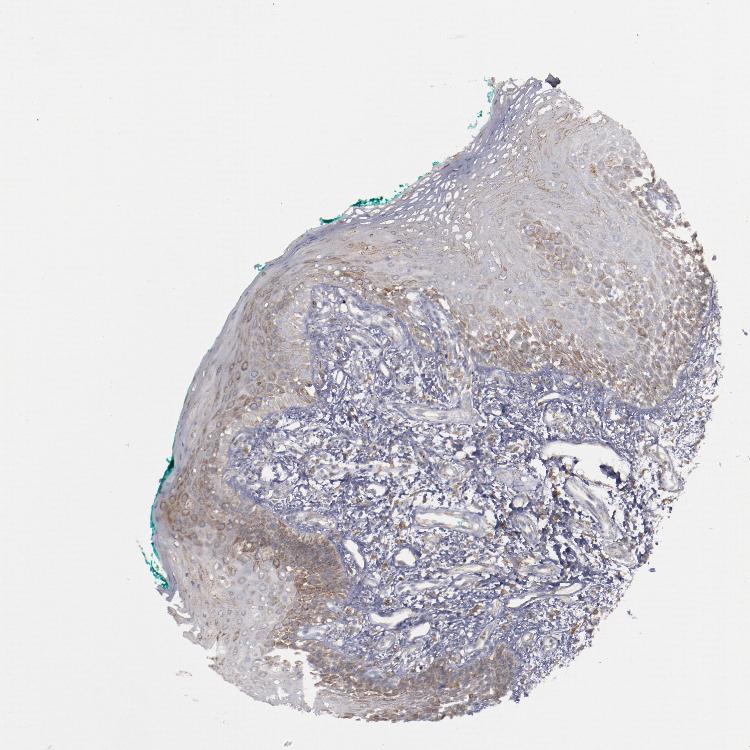

ORAL MUCOSA - Antibody stainingi

Antibody staining in the annotated cell types in the current human tissue is reported as not detected, low, medium, or high, based on conventional immunohistochemistry profiling in selected tissues. This score is based on the combination of the staining intensity and fraction of stained cells.

Each image is clickable and will lead to virtual microscopy that enables deeper exploration of all samples and also displays staining intensity scores, fraction scores and subcellular localization as well as patient and tissue information for each sample.

Antibody HPA002025Antibody CAB014894

Squamous epithelial cells LowMedium